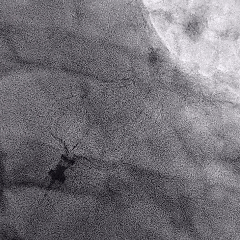

Lefort封堵器释放

封堵器释放前造影

下缘未露肩

符合Lefort释放原则,释放后造影,封堵器形态良好,未发生移动